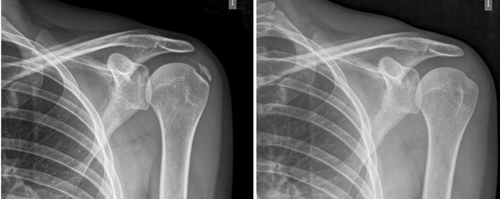

El número promedio de sesiones en nuestra serie fue de 20. El criterio para continuar o suspender el tratamiento fue la evolución radiológica y clínica (Figuras 4 y 5). Las intervenciones se realizaron hasta un máximo de 40 sesiones. Perrón trató a sus pacientes por 9 sesiones (3 sesiones semanales por 3 semanas) (14). Leduc trató con 10 sesiones (3 por semana las dos primeras semanas; y luego una semanal por 4 semanas) (15). Rioja-Toro trató a sus pacientes por 40 sesiones (5 veces por semana) y los evaluó a las 20 y a las 40 sesiones (3). Chico-Álvarez trató a sus pacientes entre 15 y 30 sesiones dependiendo de la evolución radiológica (5 veces por semana) (1).

Fig. 5. Paciente mujer de 44 años, con tendinitis calcificante de supraespinoso izquierdo, de tipo resortivo, quien tras 20 sesiones de iontoforesis disminuyó el dolor medido por EVA de 10/10 a 4/10, y la calcificación de 22 mm a 0 mm (desaparición completa).